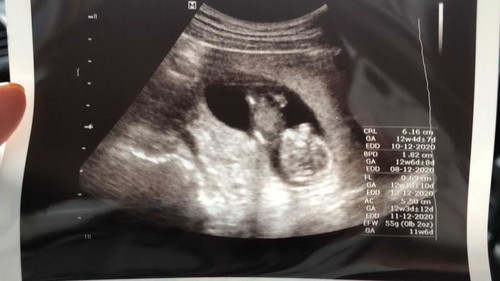

13 weeks

Hi saja je nak share my feeling. Haritu mase first scan 4 weeks nampak kantung je and kita tunggu sabar je until cukup habis 1st trimester untuk scan. Scan-scan je nampak baby tertonggeng mcm tu. Perasaan masa sebaknya tengok betul la ade little human dalam diri kita ni. First baby la katakan. Tapi orang cakap jangan happy sgt sbb jauh lagi perjalanan. Buat lebih terharu bila kita bercakap je kan, kita nampak baby tendang2 kaki die ☺️☺️ Minta doakan semoga baby terus sihat sepanjang dalam kandungan, selamat dilahirkan dan membesar menjadi sihat, cerdik, sedap mata memandang dan disenangi. Amin.